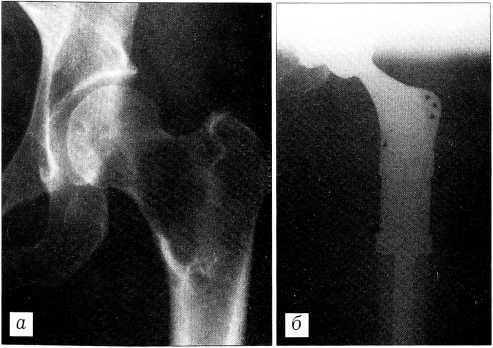

Больная Б., 56 лет, госпитализирована по поводу солитарного метастаза в проксимальном отделе левой бедренной кости с патологическим переломом (рис. 6, а). Из анамнеза известно, что в 1988 г. получала комбинированное лечение по поводу рака молочной железы, в 1990 и 1992 гг. проходила повторное лечение по поводу местных рецидивов в послеоперационном рубце. Страдает тяжелым ревматическим митрально-аортальным пороком сердца с выраженной недостаточностью кровообращения, легочной гипертензией и нарушениями ритма. Больной показано протезирование клапанов сердца, однако операция не проводилась из-за наличия онкологической патологии.

4.11.98 выполнена резекция проксимального суставного конца бедренной кости с эндопротезированием (рис. 6, б). Операция и послеоперационный период прошли без осложнений. Через 3 мес больная оперирована в кардиохирургическом стационаре, где произведено протезирование клапанов. Через 1,5 года после операции чувствует себя хорошо, работает по специальности. Таким образом, для этой больной были решены две задачи — продление жизни и улучшение ее качества.

Рис. 6. Рентгенограммы больной Б. Метастатическое поражение проксимального отдела бедра с патологическим переломом. а — до операции; б — после операции.